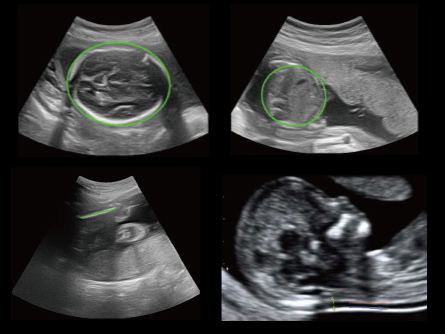

CHISON lleva la Salud de la Mujer a nuevos niveles con máquinas de ultrasonido dedicadas. Diseñadas para ginecólogos y obstetras, nuestros sistemas ofrecen una claridad sin igual en la imagen, respaldando diagnósticos seguros. Desde la atención prenatal hasta los exámenes ginecológicos, las soluciones de ultrasonido de Salud de la Mujer de CHISON proporcionan una calidad de imagen superior, mejorando la comprensión de anatomías complejas. Eleve la atención al paciente con nuestra tecnología fácil de usar y eficiente.